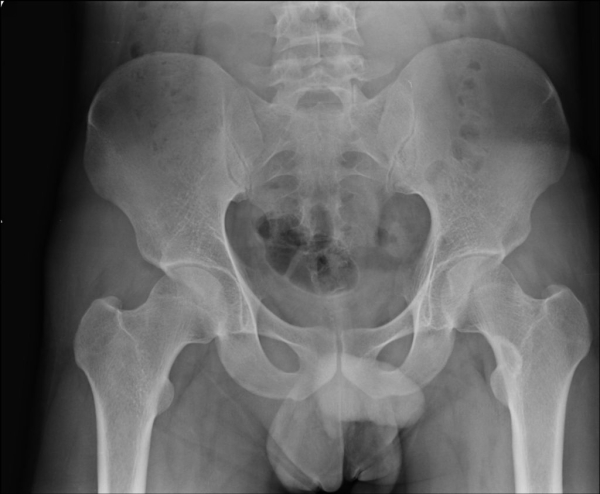

• нижний конец большеберцовой кости;

• лучевые, метатарзальные, пяточные кости;

• ребра;

• длинные трубчатые плечевые и тазобедренные кости;

• область позвоночника;

• кости черепа;

• мелкие кости кистей или стоп.